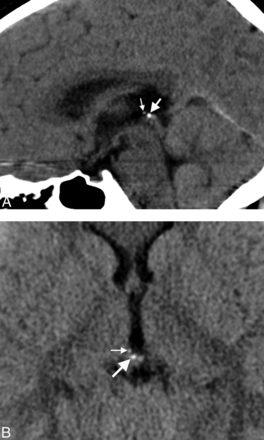

A, Midline sagittal head CT image from an 8-year-old child obtained for headache, demonstrating calcifications in both the pineal gland (large arrow) and habenular complex (small arrow). Habenular calcifications are centered anterosuperior and lateral to the pineal base. B, Axial head CT image through the epithalamus from an 8-year-old child performed for headache, showing pineal gland (large arrow) and habenular (small arrow) calcifications. Habenular calcifications are centered anterolateral to the pineal base.

Habenular calcifications were found in 10% (n = 50; age range, 2.8–8.8 years; median, 7 years; Fig 2).

This study has several limitations. Calcium detection is inherently limited by CT section thickness; therefore, intracranial calcifications may have been underestimated. However, we believe this underestimation to be of little clinical importance because thinner section soft-tissue algorithm images are not currently part of most practices. Despite their distinctive locations, pineal and habenular calcifications can sometimes be difficult to separate visually; this problem could have resulted in misclassification in some instances (Fig 2). Pineal cysts are common in the age group in our study and can distort regional anatomy.7 We found pineal cysts in 3% of our patient cohort, ranging from 4 to 15 mm; however, only 4 of these patients had epithalamic calcifications.